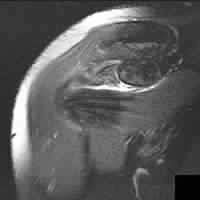

A 27-year-old professional volleyball attacker complains of subtle posterior shoulder pain and a subjective decrease in hitting power. Physical exam reveals normal active elevation, 5/5 strength in shoulder abduction, but notable weakness (3/5) in external rotation with the arm at the side. MRI of the shoulder is ordered. Based on the physical exam findings, where is the isolated neural compression most likely located, and what is the classic associated pathologic finding?

Explanation

The patient exhibits isolated weakness in external rotation (infraspinatus) with preserved abduction (supraspinatus). This indicates suprascapular nerve entrapment distal to the branches supplying the supraspinatus, specifically at the spinoglenoid notch. In overhead athletes, this is classically associated with a paralabral cyst extending from a posterior superior labral tear (SLAP lesion).